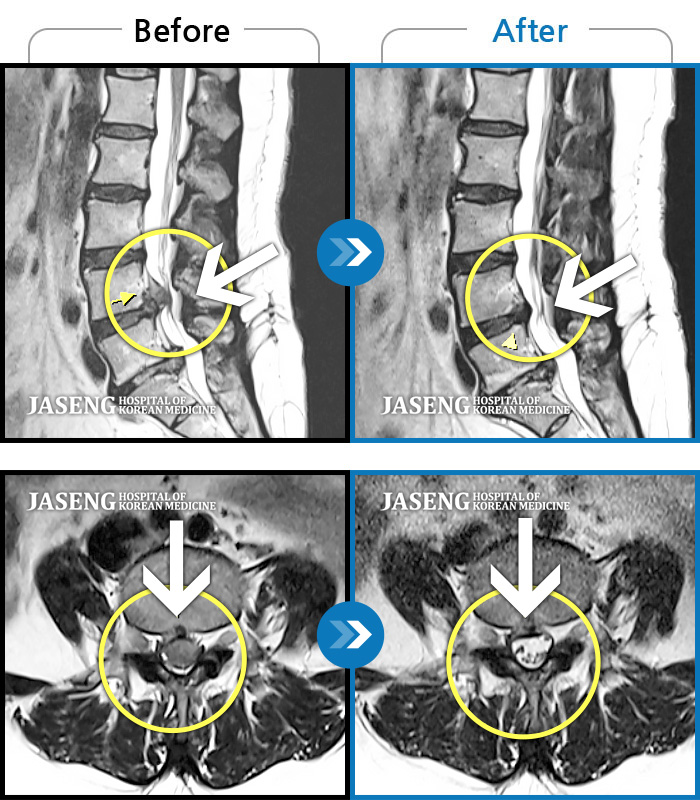

MRI 치료사례

허리 우측에서 발바닥까지 통증, 누워있을 때 당기는 증상